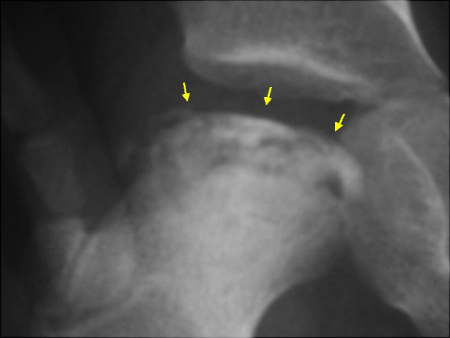

- FRAGMENTATIE (fig. 1): Het dood bot wordt door het lichaam afgebroken en vervangen met nieuwe botvormende cellen die voor de nieuwe botvorming zullen zorgen. De heupkop kan nu remodelleren en opnieuw een rondere vorm aannemen. Deze fase kan van één tot drie jaren duren.

- REOSSIFICATIE (fig. 2): De heupkop blijft verder nieuw bot vormen en steviger worden. Deze fase kan tot drie jaren duren.